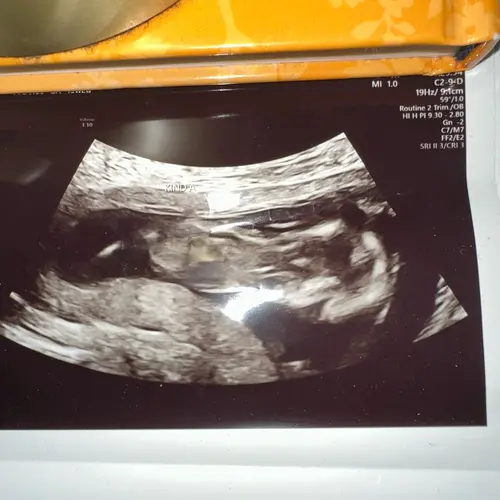

Is het hier wel beter op te zien?

Heb je nog een andere,